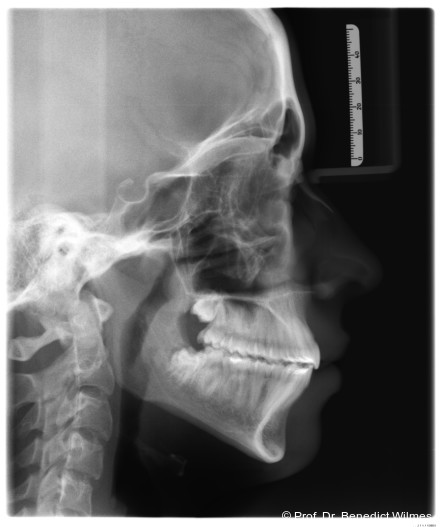

Eine 13-jährige Patientin stellte sich mit beidseitigem Kreuzbiss, einem anterioren offenen Biss und einer Angle Klasse II vor. Das viszerale Schluckmuster wurde mittels logopädischer Maßnahmen umgestellt, der offene Biss persistierte jedoch (Abb. 3a–l).

Klinisches Prozedere

Die initiale Behandlung erfolgte mit einer CAD/CAM Hybrid Hyrax zur Expansion des Oberkiefers, verankert an zwei paramedianen Miniimplantaten (Abb. 4, Benefit, 2,0 x 9,0 mm). Anstelle klassischer Molarenbänder wurden Shells (geklebte Kappen) verwendet, wodurch die beiden Schritte Separieren und Anpassen von Molarenbändern entfallen. Die Miniimplantate und die Apparatur wurden dank eines Inser­tionsguides in nur einer Sitzung eingesetzt.